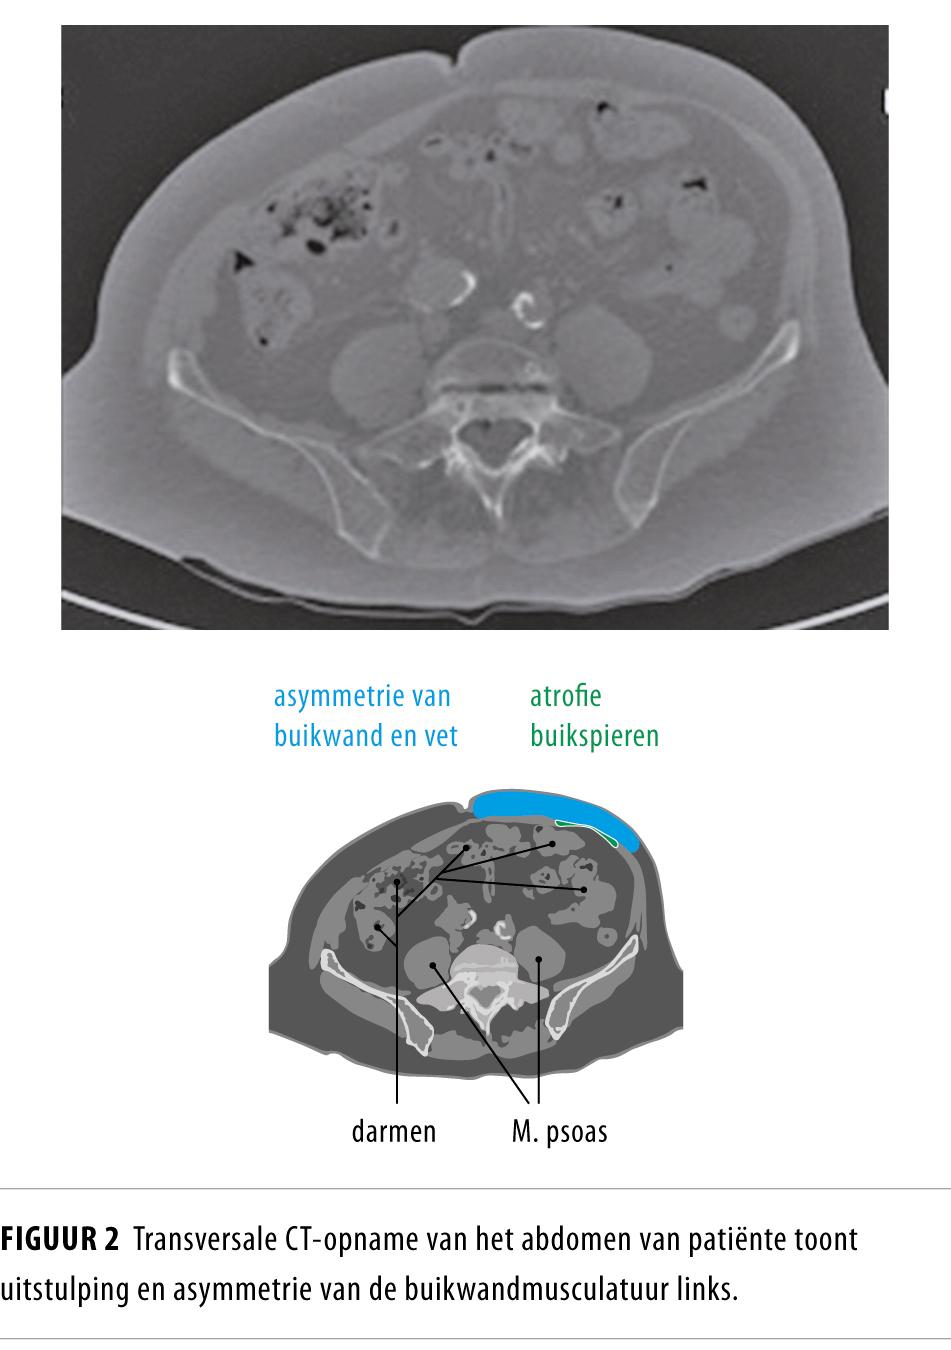

Een 73-jarige vrouw kwam bij de chirurg met een pijnlijke zwelling linksonder in de buik. Ter plaatse van de zwelling had zij een aantal maanden eerder herpes zoster doorgemaakt. Op een CT-scan was asymmetrie van de buikwandmusculatuur te zien, waardoor we een verband tussen motorische betrokkenheid van de herpes zoster en de abdominale zwelling vermoedden. Emg toonde denervatie van de aangedane buikwandspier, waarmee het verband met herpes zoster in dat dermatoom werd bevestigd.